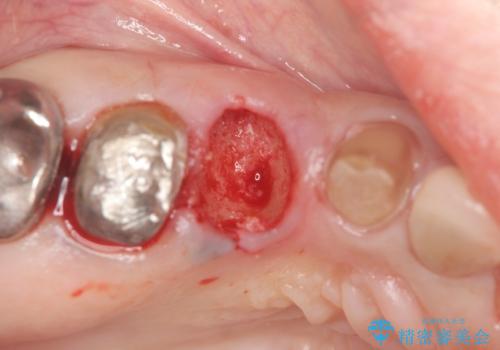

また単純に抜歯のみを行うと歯ぐきが大きく凹み、ブリッジの清掃性が損なわれることが予想されるため、抜歯時に歯槽堤保存術を行い

清掃性の高い仕上がりとなるよう配慮しています。